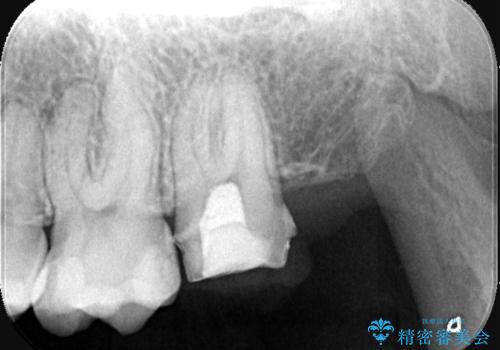

- 虫歯の治療を希望されました。一番奥の歯は虫歯が深かったことから神経を部分的に残す治療法(生活歯髄療法)や神経の治療(根管治療)についても説明し、治療介入をしました。

左上7番は治療前の神経の検査では正常の範囲内の値を示しました。虫歯を削っていったところ神経まで到達したため、神経を部分的に残す治療法を選択しました。その後痛み等症状が出ず、また、神経の反応も正常であったため、被せ物にしています。